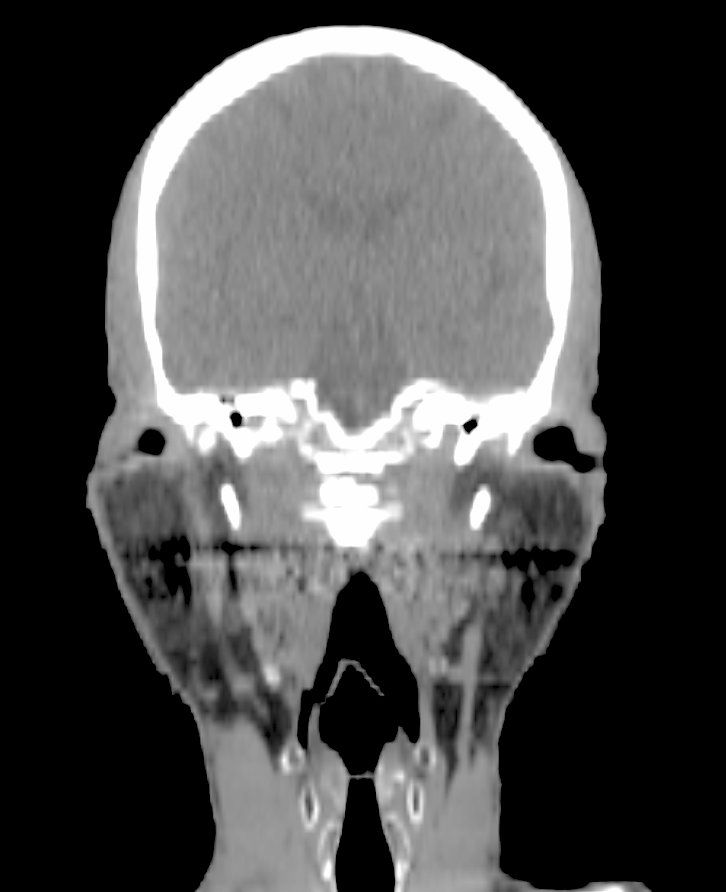

The diagnostic evaluation consists mainly of ultrasound scan, CT, and/or MRI showing multiple thin walled cysts.4 (See CT scans above.)